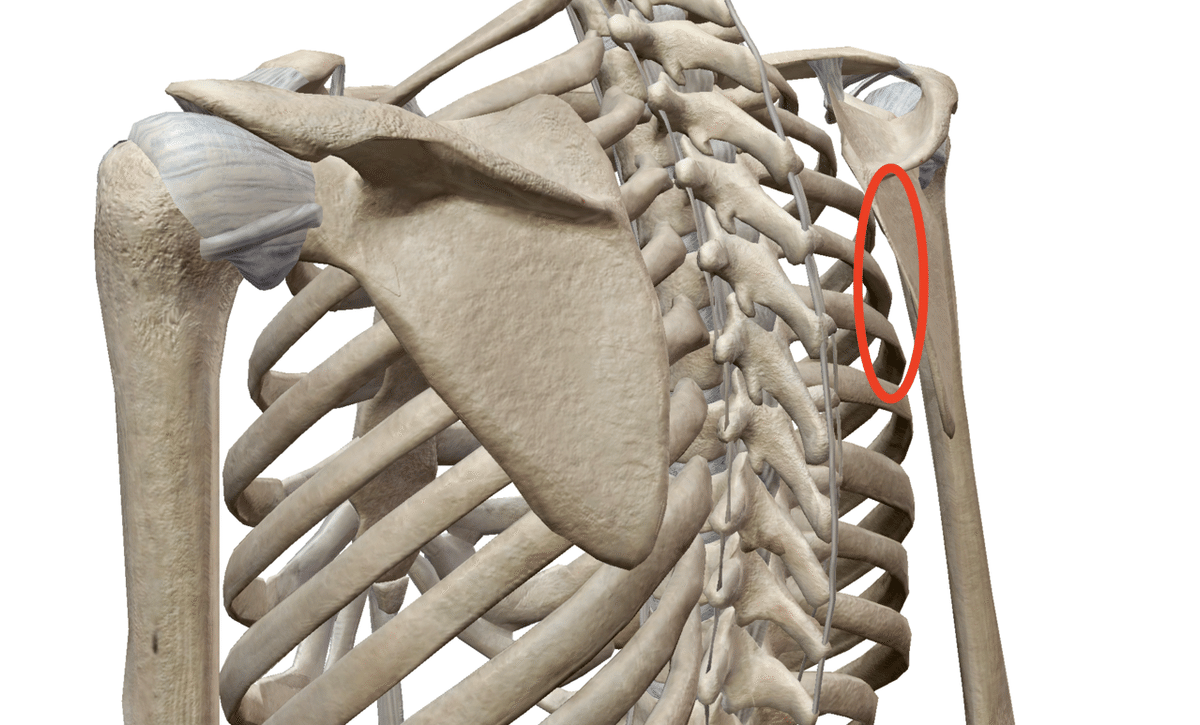

ここの関節は他の関節とは違い、特殊な構造になっています。

ではどのような特徴かと言うと「位置覚が少ない」という特徴です。

位置覚とは、体の各部位と肩甲骨がどの位置関係にあるかということを感知するセンサーのようなものです。

このセンサーが少ないと

・肩甲骨がどのように動いているのか

・そして肩甲骨がどの位置にあるのか

これが全然わかりません。